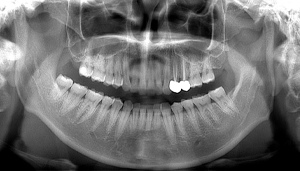

左上下の親知らずが

大きな虫歯になっていた症例

- 抜歯前写真(レントゲン、CT等)

- 抜去歯の写真

| 年齢 | 20代・女性 |

|---|---|

| 主訴 | 右下の親知らずを抜きたい |

| 親知らずの生え方 | 半分埋まっている |

| 抜歯時間 | 60分 |

| 費用 | 約6,000円(CT代含む) |

| 抜歯内容 | 右下親知らずが半分埋まっているため、汚れが溜まりやすく気になる為患者様のご希望により抜歯しました。 このケースでは事前にCTを撮影し、歯の位置、神経との位置関係を確認してから抜歯を行っています。 抜歯後、一週間は腫れと痛みがありましたが鎮痛剤を飲んで対応して頂き、糸取りをする頃には痛みや腫れは無くなり、患者様も安心しておられました。 |